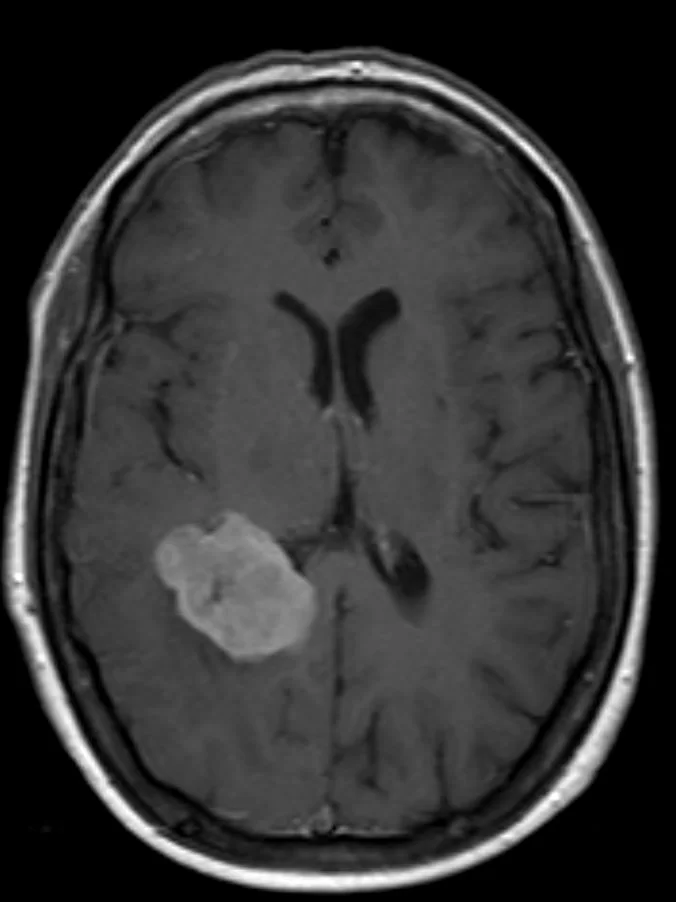

Ασθενής άνδρας, 31 ετών με επεισόδια κεφαλαλγίας. H Μαγνητική Τομογραφία εγκεφάλου ανέδειξε εκτεταμένη χωροκατακτητική εξεργασία δεξιά κροταφικά με πίεση επί του σύστοιχου κροταφικού κέρατος και

Περισσότερα